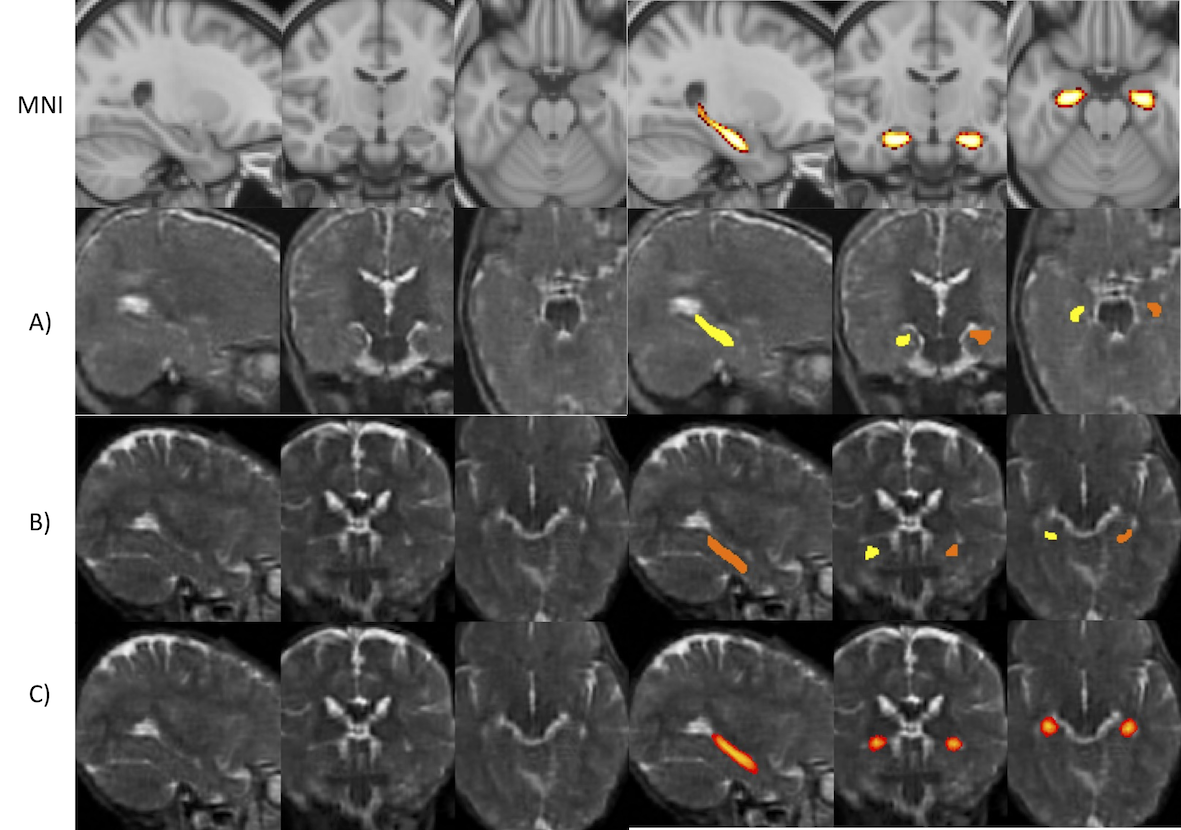

Figure 5: Example hippocampal segmentations. Row 1: MNI T1 2mm template with the Harvard-Oxford probabilistic atlas, thresholded at 0.5. A): Example A showing a sample the 3D UNet repeatedly performed well (DSC >>> 0.6) on with the tail of the atlas touching the ventricle. B) Example B showing a sample where the 3D UNet performed poorly (DSC >>> 0.1), where the localisation of the hippocampus in the target appears different to the MNI template and sample A, with the label not reaching the ventricles. C) Example B with the average hippocampus mask registered to it, showing that the average hippocampus mask is located disjoint to the manual segmentation mask.

Training and evaluation of the DL-based models were affected by the quality of the manual masks: unsurprisingly given the low contrast and relatively poor image quality, the quality of the training masks varied, biasing results. For instance, some samples appear to have labels which mislocalise the hippocampus (Fig. 5) where it can be seen that the example B’s mask appears to be shifted lower than the expected location when considering the other examples and the average hippocampus mask registered to that subject.